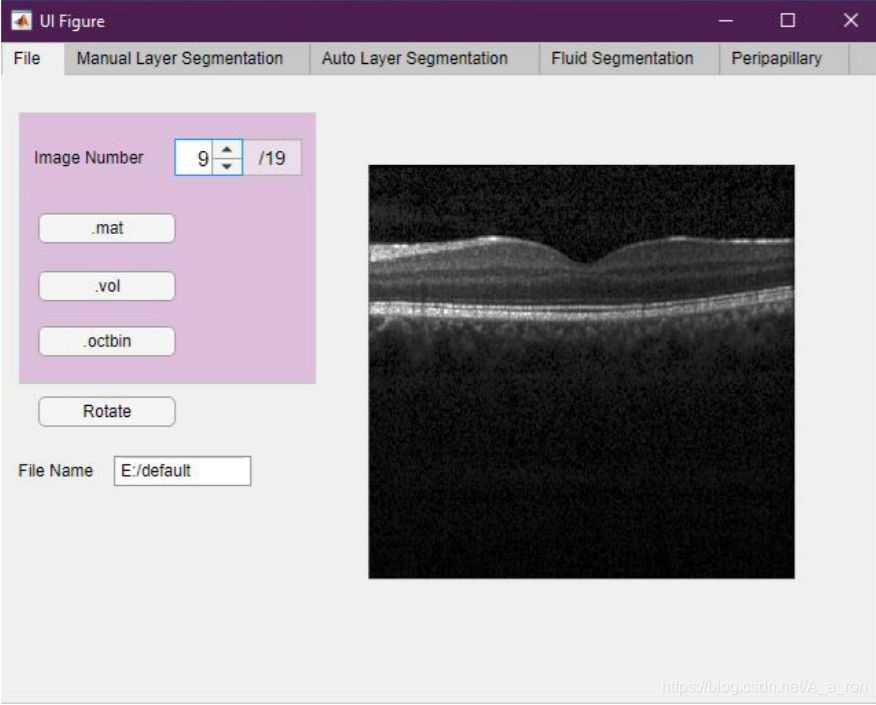

5. Livelayer

Livelayer: A Semi-Automatic Software for Segmentation of Layers and Objects in Optical Coherence Tomography Images,一个基于Matlab的半自动的视网膜层次分割软件。目前该论文仅仅发在Arxiv上(2020年3月份),没有提供网站介绍和下载链接。论文中给出的界面如下:

手动分割界面:

有需要的同学可以关注下这个论文的后续进展。